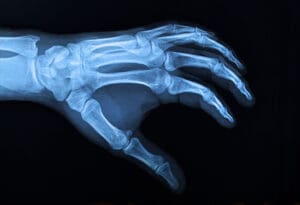

Tokom operacije koja je trajala 13 sati, hirurzi medicinskog univerziteta u Wroclawu su presadili šaku preminulog donora na Piotrov ručni zglob. Koristili su titanijumske šrafove i pločice za povezivanje kostiju prije nego što su povezali mišiće, tetive, nerve i krvne sudove.